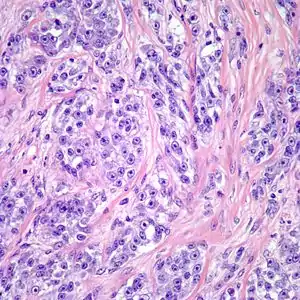

Clear cell sarcoma. Tumor cells with prominent nucleoli and clear cytoplasm are arranged in well-defined nests surrounded by dense fibrous stroma.

Despite the name clear cell sarcoma, the tumor cells do not necessarily need to have clear cytoplasm. The lesion has a distinctly nested growth pattern with a mixture of spindle, epithelioid and tumor giant cells. Approximately two thirds of the tumors contain melanin pigment. Clear cell sarcoma, similar to melanoma, has consistent positivity for S-100, HMB-45, and MITF.[5]